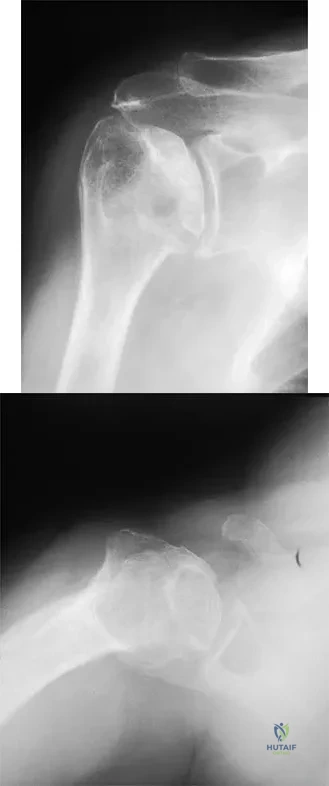

A 45-year-old woman has had progressive right shoulder pain for the past 6 months. She notes that the pain disrupts her sleep, she has pain at rest that requires the use of narcotic analgesics, and she has limited use of her left shoulder for most activities of daily living. History reveals the use of corticosteroids for systemic lupus erythematosus. Examination shows diminished range of motion. Radiographs of the right shoulder are shown in Figures 4a and 4b. Treatment should consist of

Explanation